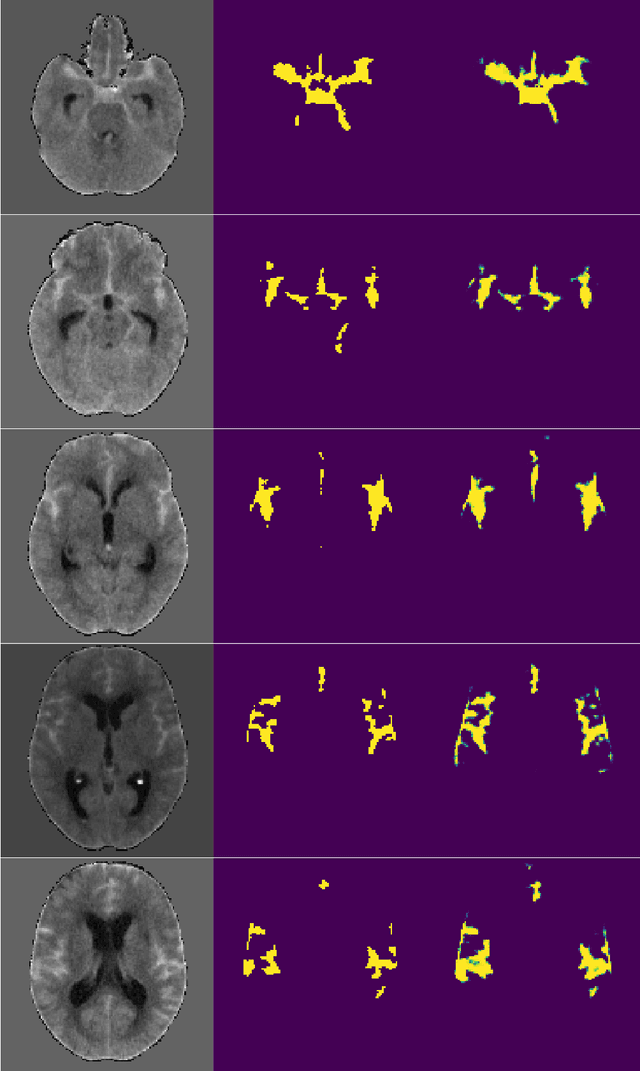

Abstract:Glioblastoma, a highly aggressive primary brain tumor, is associated with poor patient outcomes. Although magnetic resonance imaging (MRI) plays a critical role in diagnosing, characterizing, and forecasting glioblastoma progression, public MRI repositories present significant drawbacks, including insufficient postoperative and follow-up studies as well as expert tumor segmentations. To address these issues, we present the "R\'io Hortega University Hospital Glioblastoma Dataset (RHUH-GBM)," a collection of multiparametric MRI images, volumetric assessments, molecular data, and survival details for glioblastoma patients who underwent total or near-total enhancing tumor resection. The dataset features expert-corrected segmentations of tumor subregions, offering valuable ground truth data for developing algorithms for postoperative and follow-up MRI scans. The public release of the RHUH-GBM dataset significantly contributes to glioblastoma research, enabling the scientific community to study recurrence patterns and develop new diagnostic and prognostic models. This may result in more personalized, effective treatments and ultimately improved patient outcomes.